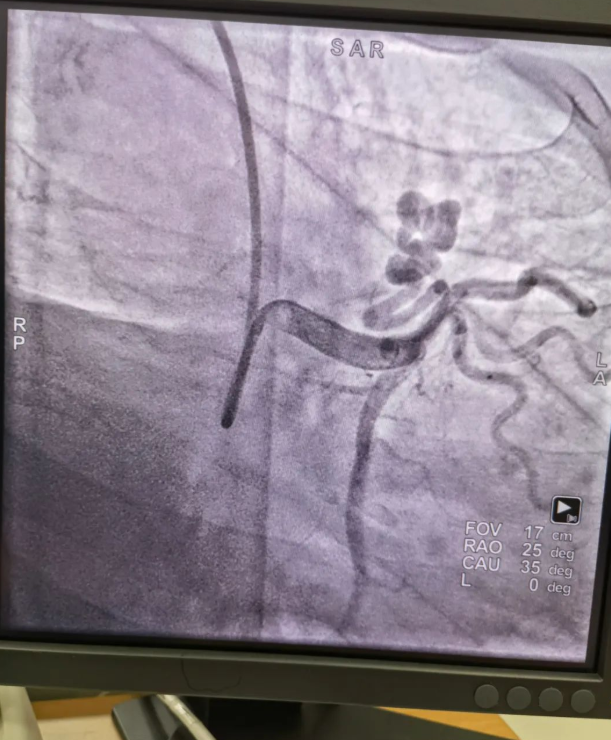

不久前,來自新疆的患者石先生去年至今反復胸悶、氣短、胸痛,就診于新疆某院,懷疑“冠心病”,住院行冠狀動脈造影術,石先生造影提示“冠狀動脈肺動脈瘺”,而他并非“冠心病”,所以給予的“冠心病”治療,效果不佳。出院后仍反復出現(xiàn)胸痛、胸悶、氣短等癥狀,經(jīng)親友介紹了解到西安國際醫(yī)學中心醫(yī)院心臟病醫(yī)院心臟內(nèi)科二病區(qū)曾廣偉主任,多年來潛心研究心臟病介入治療,成功主刀救治了許許多多高危復雜病例,尤其是在先心病及結構性心臟病封堵,以及冠心病、心律失常射頻消融及起搏治療等方面積累了豐富的診療經(jīng)驗。

此病例罕見,在曾廣偉從醫(yī)18年生涯里曾碰到有2個印象深刻的病例,患者分別是53歲和66歲,當時建議患者入院進行動脈瘺的封堵術,但患者和家屬考慮到這個手術案例極少,風險也高,均未接受手術治療建議,只是能采取藥物保守治療,出院后隨訪得知患者癥狀緩解效果不佳,后來在隨訪中也與53歲患者失去了聯(lián)系,而66歲患者因冠狀動脈肺動脈瘺出現(xiàn)反復心衰,在當?shù)蒯t(yī)院藥物治療,短短2年時間,患者因為動脈瘺未及時手術失去了生命。所以此次患者石先生到訪,曾廣偉主任在詳細掌握病例資料基礎上,果斷建議進行動脈瘺的封堵術治療,為了提高手術成功率和精準度,曾廣偉主任搜集相關診療資料,反復推演論證,經(jīng)過相當充足的準備工作,于5月18日成功進行了封堵手術,完全堵上了瘺口。

患者術后第2天,已經(jīng)沒有明顯的胸悶、氣短、胸痛等癥狀,目前身體狀態(tài)良好。本次手術曾廣偉主任及其團隊,采取從右手臂一根血管進入,并在2小時之內(nèi)完美封堵,創(chuàng)口小,痛苦小。手術雖然難度大、風險高,相關案例也少,但是曾廣偉主任主刀即在巔峰,這樣一臺完美的手術靠的不是運氣,是豐富的臨床手術經(jīng)驗,扎實的專業(yè)知識儲備,以及對醫(yī)療事業(yè)的孜孜追求。

冠狀動脈瘺是指冠狀動脈與心腔、冠狀靜脈、肺動脈等的異常連接,是一種少見的先天性心臟病,發(fā)病率為1.3%。而冠狀動脈肺動脈瘺是冠狀動脈與肺動脈之間產(chǎn)生的一種血管性瘺口,導致冠狀動脈里的血液流入肺動脈里,使冠狀動脈里血液流量減少,出現(xiàn)心肌供血不足,冠狀動脈肺動脈瘺會使患者出現(xiàn)胸部疼痛、胸悶、呼吸困難、頭暈、乏力等一系列癥狀,隨著疾病不斷進展,可引發(fā)心功能的障礙和心肌缺血,肺動脈會逐漸形成肺動脈高壓,還可能導致動脈瘤的破裂,甚至威脅病人的生命安全,所以早期發(fā)現(xiàn)和治療冠狀動脈肺動脈瘺,對病人的預后改善具有重要的意義。